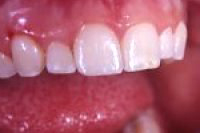

Ein seitlicher Oberkieferschneidezahn ist als sogenannter Zapfenzahn (angeboren) in die Mundhöhle durchgebrochen (Abb. 1). Nach orthodontischer Zahnbehandlung haben wir dem 16 Jahre alten Mädchen den Vorschlag gemacht, mittels zwei adhäsiv gelegten Kompositfüllungen und ohne Beschleifen den Zapfenzahn in einen natürlichen Schneidezahn umzuformen (Abb. 2).